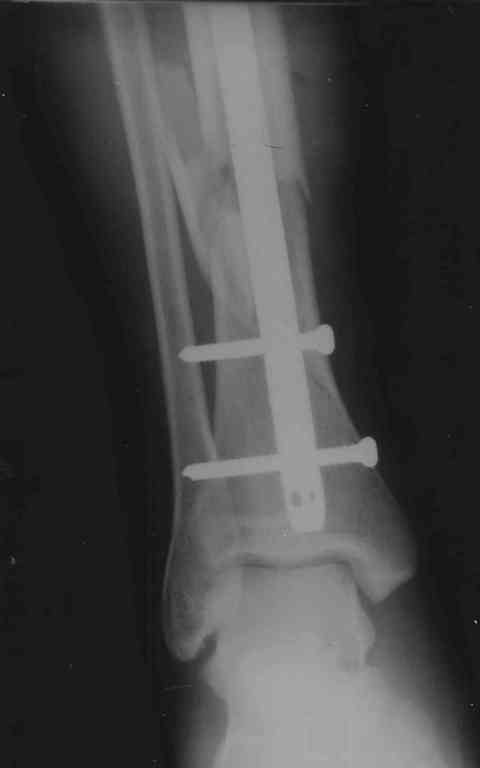

Перелом б/берцовой и малой берцовой кости в н/3 со смещением отломков |

Нужна консультация по поводу консолидации отломков б/берцовой кости после операции с остеосинтезом, все ли срастается правильно, не нужна ли повтроная операция(отломок на рис 2)по поводу отломка всавшего между большой и малой берцовой костью, или он втанет на место или раствориться,а то ощущения будто он мешает при массаже голени(болит из-за него мышца, не помешает ли при ходьбе в дальнейшем)? 1.Так же вопрос есть по ФЛК врач сказал что колено тоже повреждено-разорваны связки не полностью по словам(удалял кровь из шва под коленкой. есть твердая припухлость снизу и с внешней стороны коленного сустава,так же при лежании на поврежденной внешней стороне колена появляется боль которая пропадает при изменении положения),проведена иммобилизация коленного сустава в туторе-5 недель, после снятие подвижность в суставе около 15% от здорового коленного сустава- какие делать процедуры, чтобы потом не делать еще и опарацию на колене? очень не хочется.Мне 31 год рост 180 вес 100 , операций и заболеваний не было до этого. Зараннее спасибо за советы).

Добавляю еще снимки, после операции прошел 1 месяц, снимков сразу после операции и до нее на руки мне не дали.

По поводу перелома костей голени ничего предпринимать не нужно, все приемлемо. В сроке 2 мес. нужно посмотреть снимки и решить по нагрузке и необходимости удаления винта вверху.